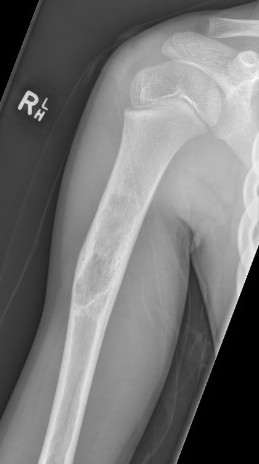

X-ray

Well-defined lucency

- thin sclerotic rim

- usually central

- thinned cortex with slight expansion

- thin internal septa

- can be multi-loculated

Fallen-Leaf (AKA fallen-fragment)

- with pathological fracture

- indicates that the lesion has no matrix and is fluid filled

Fallen leaf sign